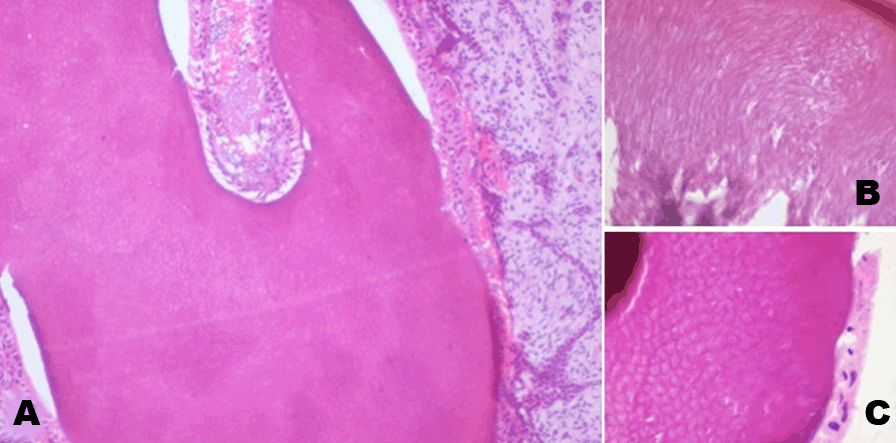

Figure 4: (A) Histologic section showing presence of enamel organ comprised mainly of enamel and dental papilla on a primitive ectomesenchymal background with strands and cords of odontogenic epithelium of about 2–3 cells in thickness. (H&E stain, x100) (B) Higher magnification showing arrangement of enamel rods. (H&E stain, x400) (C) Higher magnification of enamel showing ‘fish scale’ pattern of arrangement of the enamel rods. (H&E stain, x400).

At multiple areas the dental lamina like strands gave rise to dental follicles very similar to advanced bell stage, showing the presence of ameloblasts, odontoblasts along with enamel matrix and dentin formation. Enamel was partially mineralized or was seen as an un-mineralized matrix. Mineralized enamel showed the presence of well-formed enamel prisms (Figure 4). Dental follicles showed the presence of thick tubular predentin like areas lined by odontoblasts. The area of dentin next to the enamel is well mineralized with globular dentin. Different areas showed dental follicles in various stages of tooth development. The enamel organs bore resemblance to cap, bell and advanced bell stages very frequently. No evidence of cementum like tissue was seen, but primitive pulp in the form of dental papilla was observed (Figure 5). These areas appeared similar to a composite compound odontome. Based on these findings, a final diagnosis of ameloblastic fibro-odontoma was given.